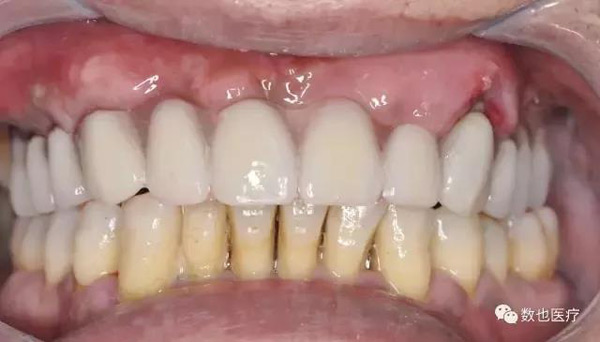

术后患者口内照